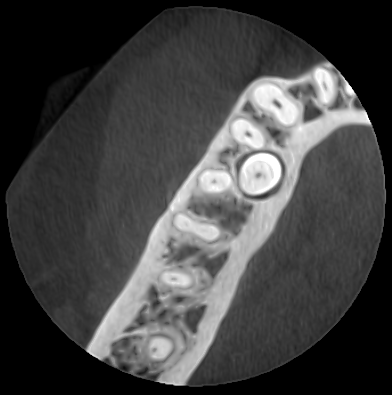

- FOV pequeño→ dientes concretos / endodoncia (5’5cm x 5’5cm)

- Endodoncia: FOV pequeño para máxima precisión